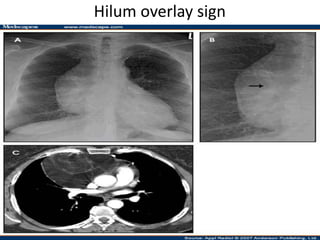

Hilum overlay sign

• Differentiates cardic enlargement from

mediastinal mass

• In mediastinal mass if Hilar vessels are seen

through the mass indicates that the mass

does not arise from hilum

• For accuracy the film should be true frontal

,slight obliquity may project normal

pulmonary artery medialy